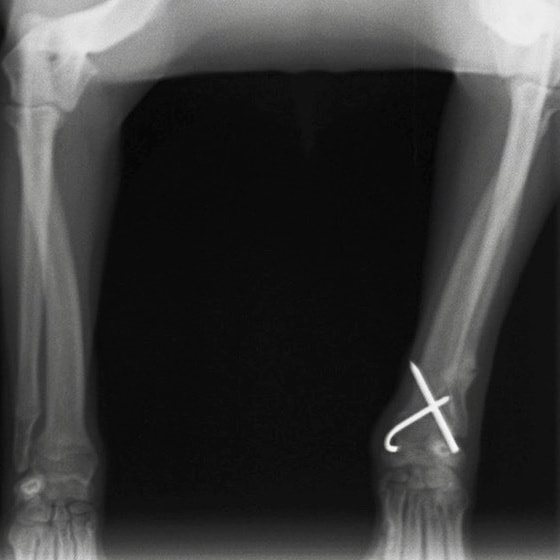

症例3:キルシュナーワイヤーのピンニングによる整復

ペルシャ猫 11ヶ月齢 雄

他院にて左大腿骨遠位の成長板骨折(salter-harrisⅠ型)が認められており、治療相談を目的として来院。当院にて、キルシュナーワイヤーを用いたピンニングにより骨折部位の整復を行いました。術後の経過は良好で、現在も経過観察中です。

術前レントゲン

術後レントゲン

機器

Arthrex社のターゲティングデバイスを用いてピンニングの位置を調整することで、確実な固定を行っています。当院ではこの手術器具以外にも、人の手術にも使用される様々な器具を導入し、手術精度を高め、また医療メーカーと新しい器具の開発、試作にも取り組んでおります。